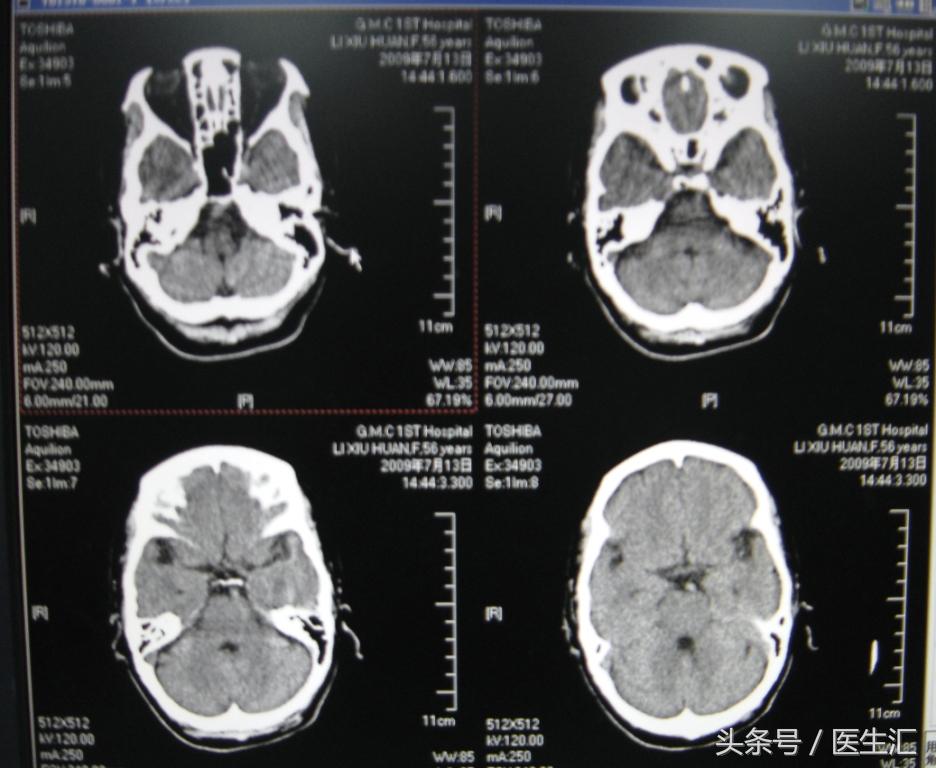

溶栓前头颅CT(见图1)

专家判读:左侧内囊区可见低密度影。两侧大脑半球及岛叶未见明显水肿低密度或者脑出血的高信号。